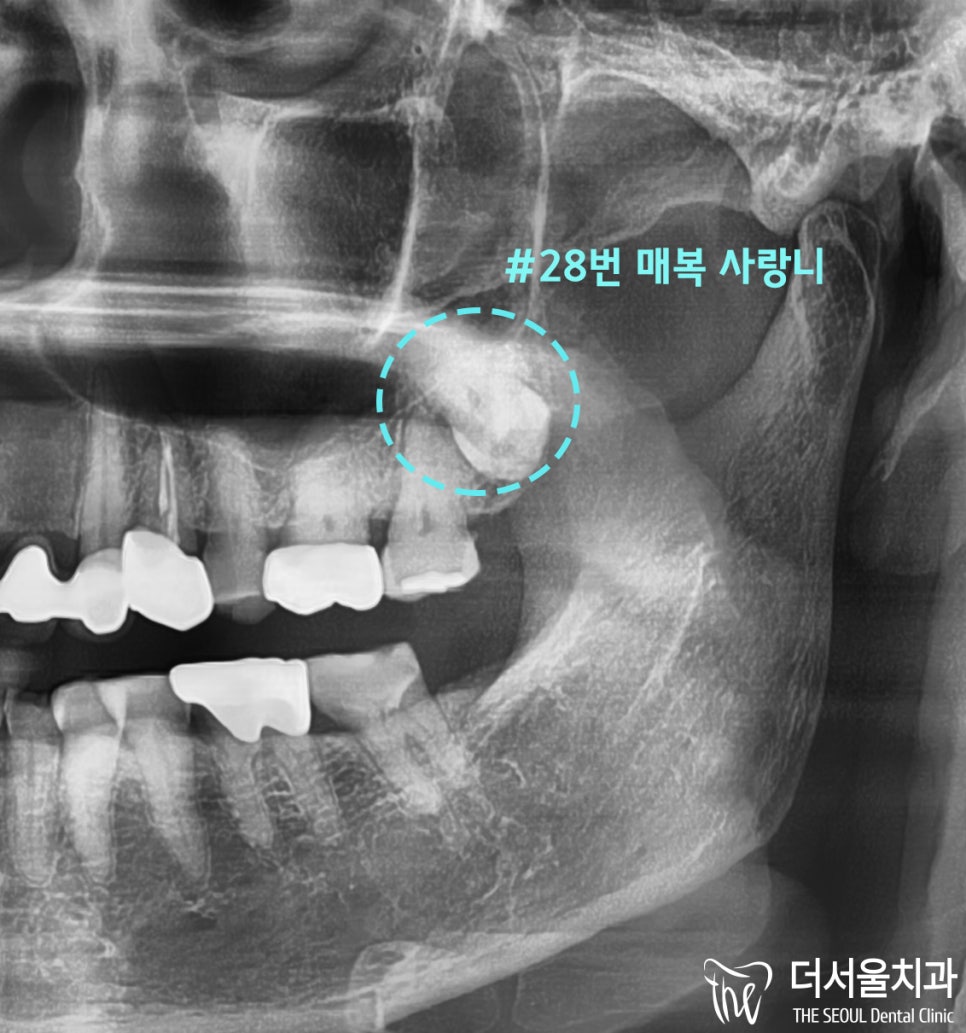

해당 내용을 토대로

파노라마 엑스레이를 찍어본 결과

사랑니가 매복된 형태로 자리하고 있었습니다.

이와 더불어

바로 앞쪽에 있는 어금니와

거의 맞닿아 있는 수준으로 가까웠습니다.